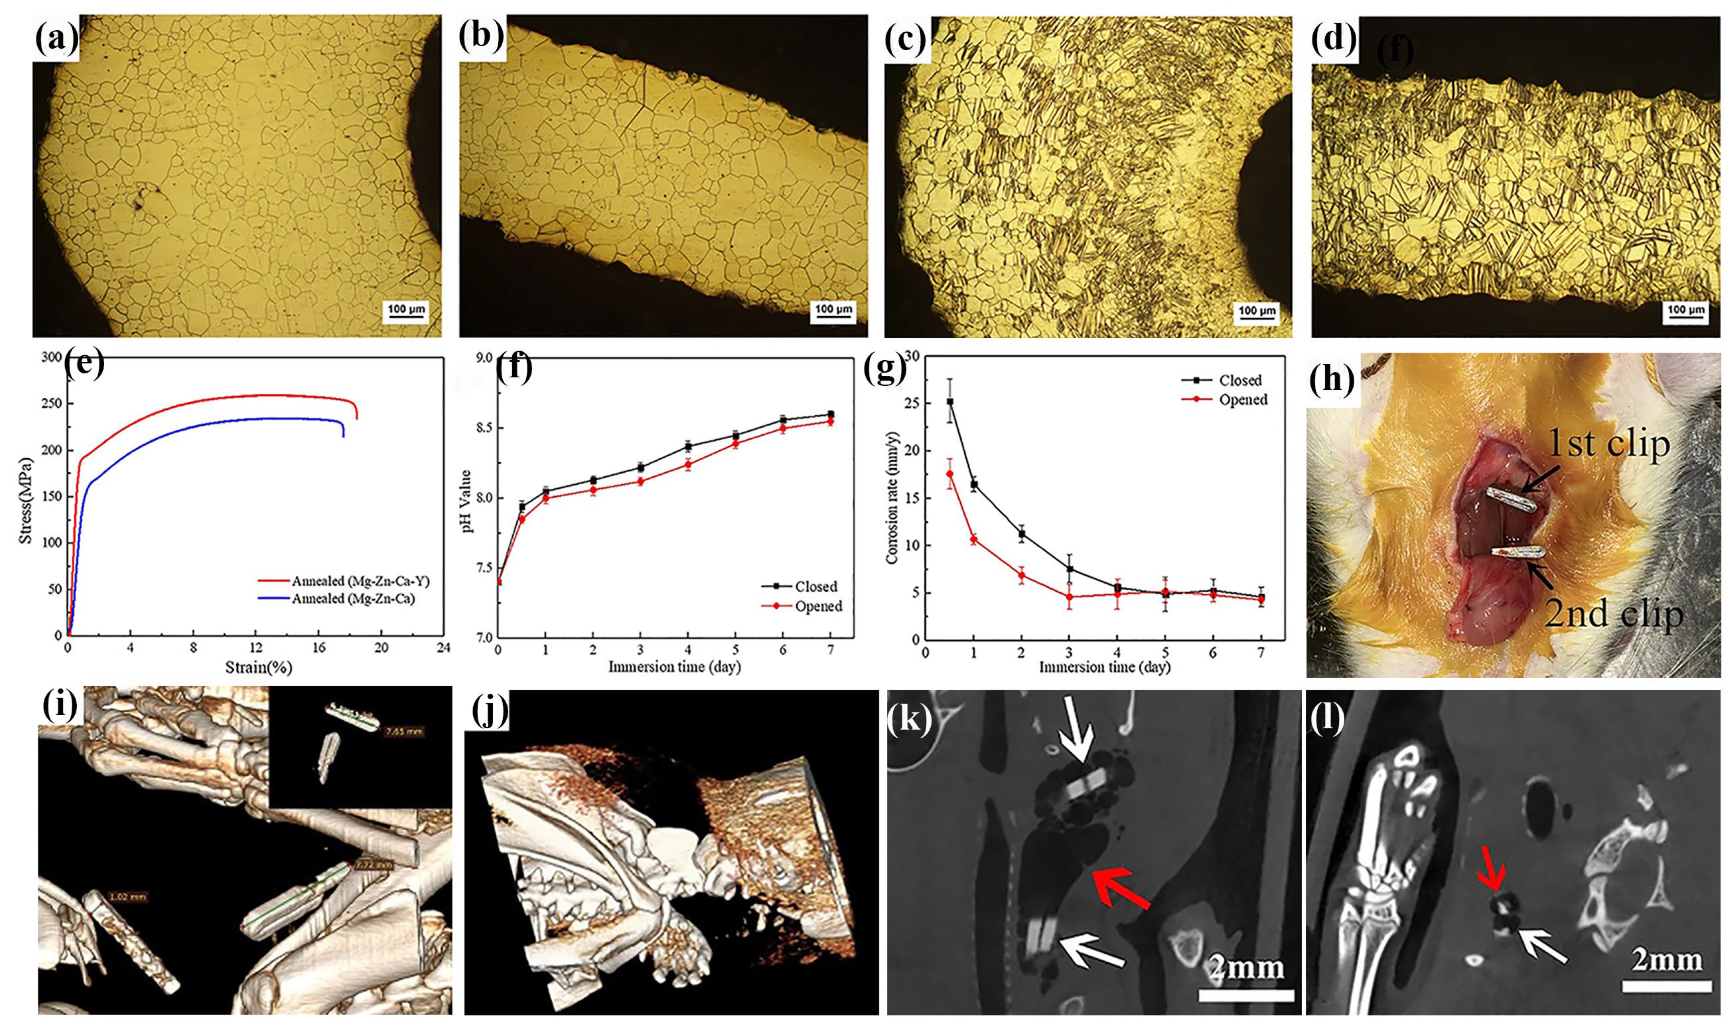

3.1. Hemostatic Clip